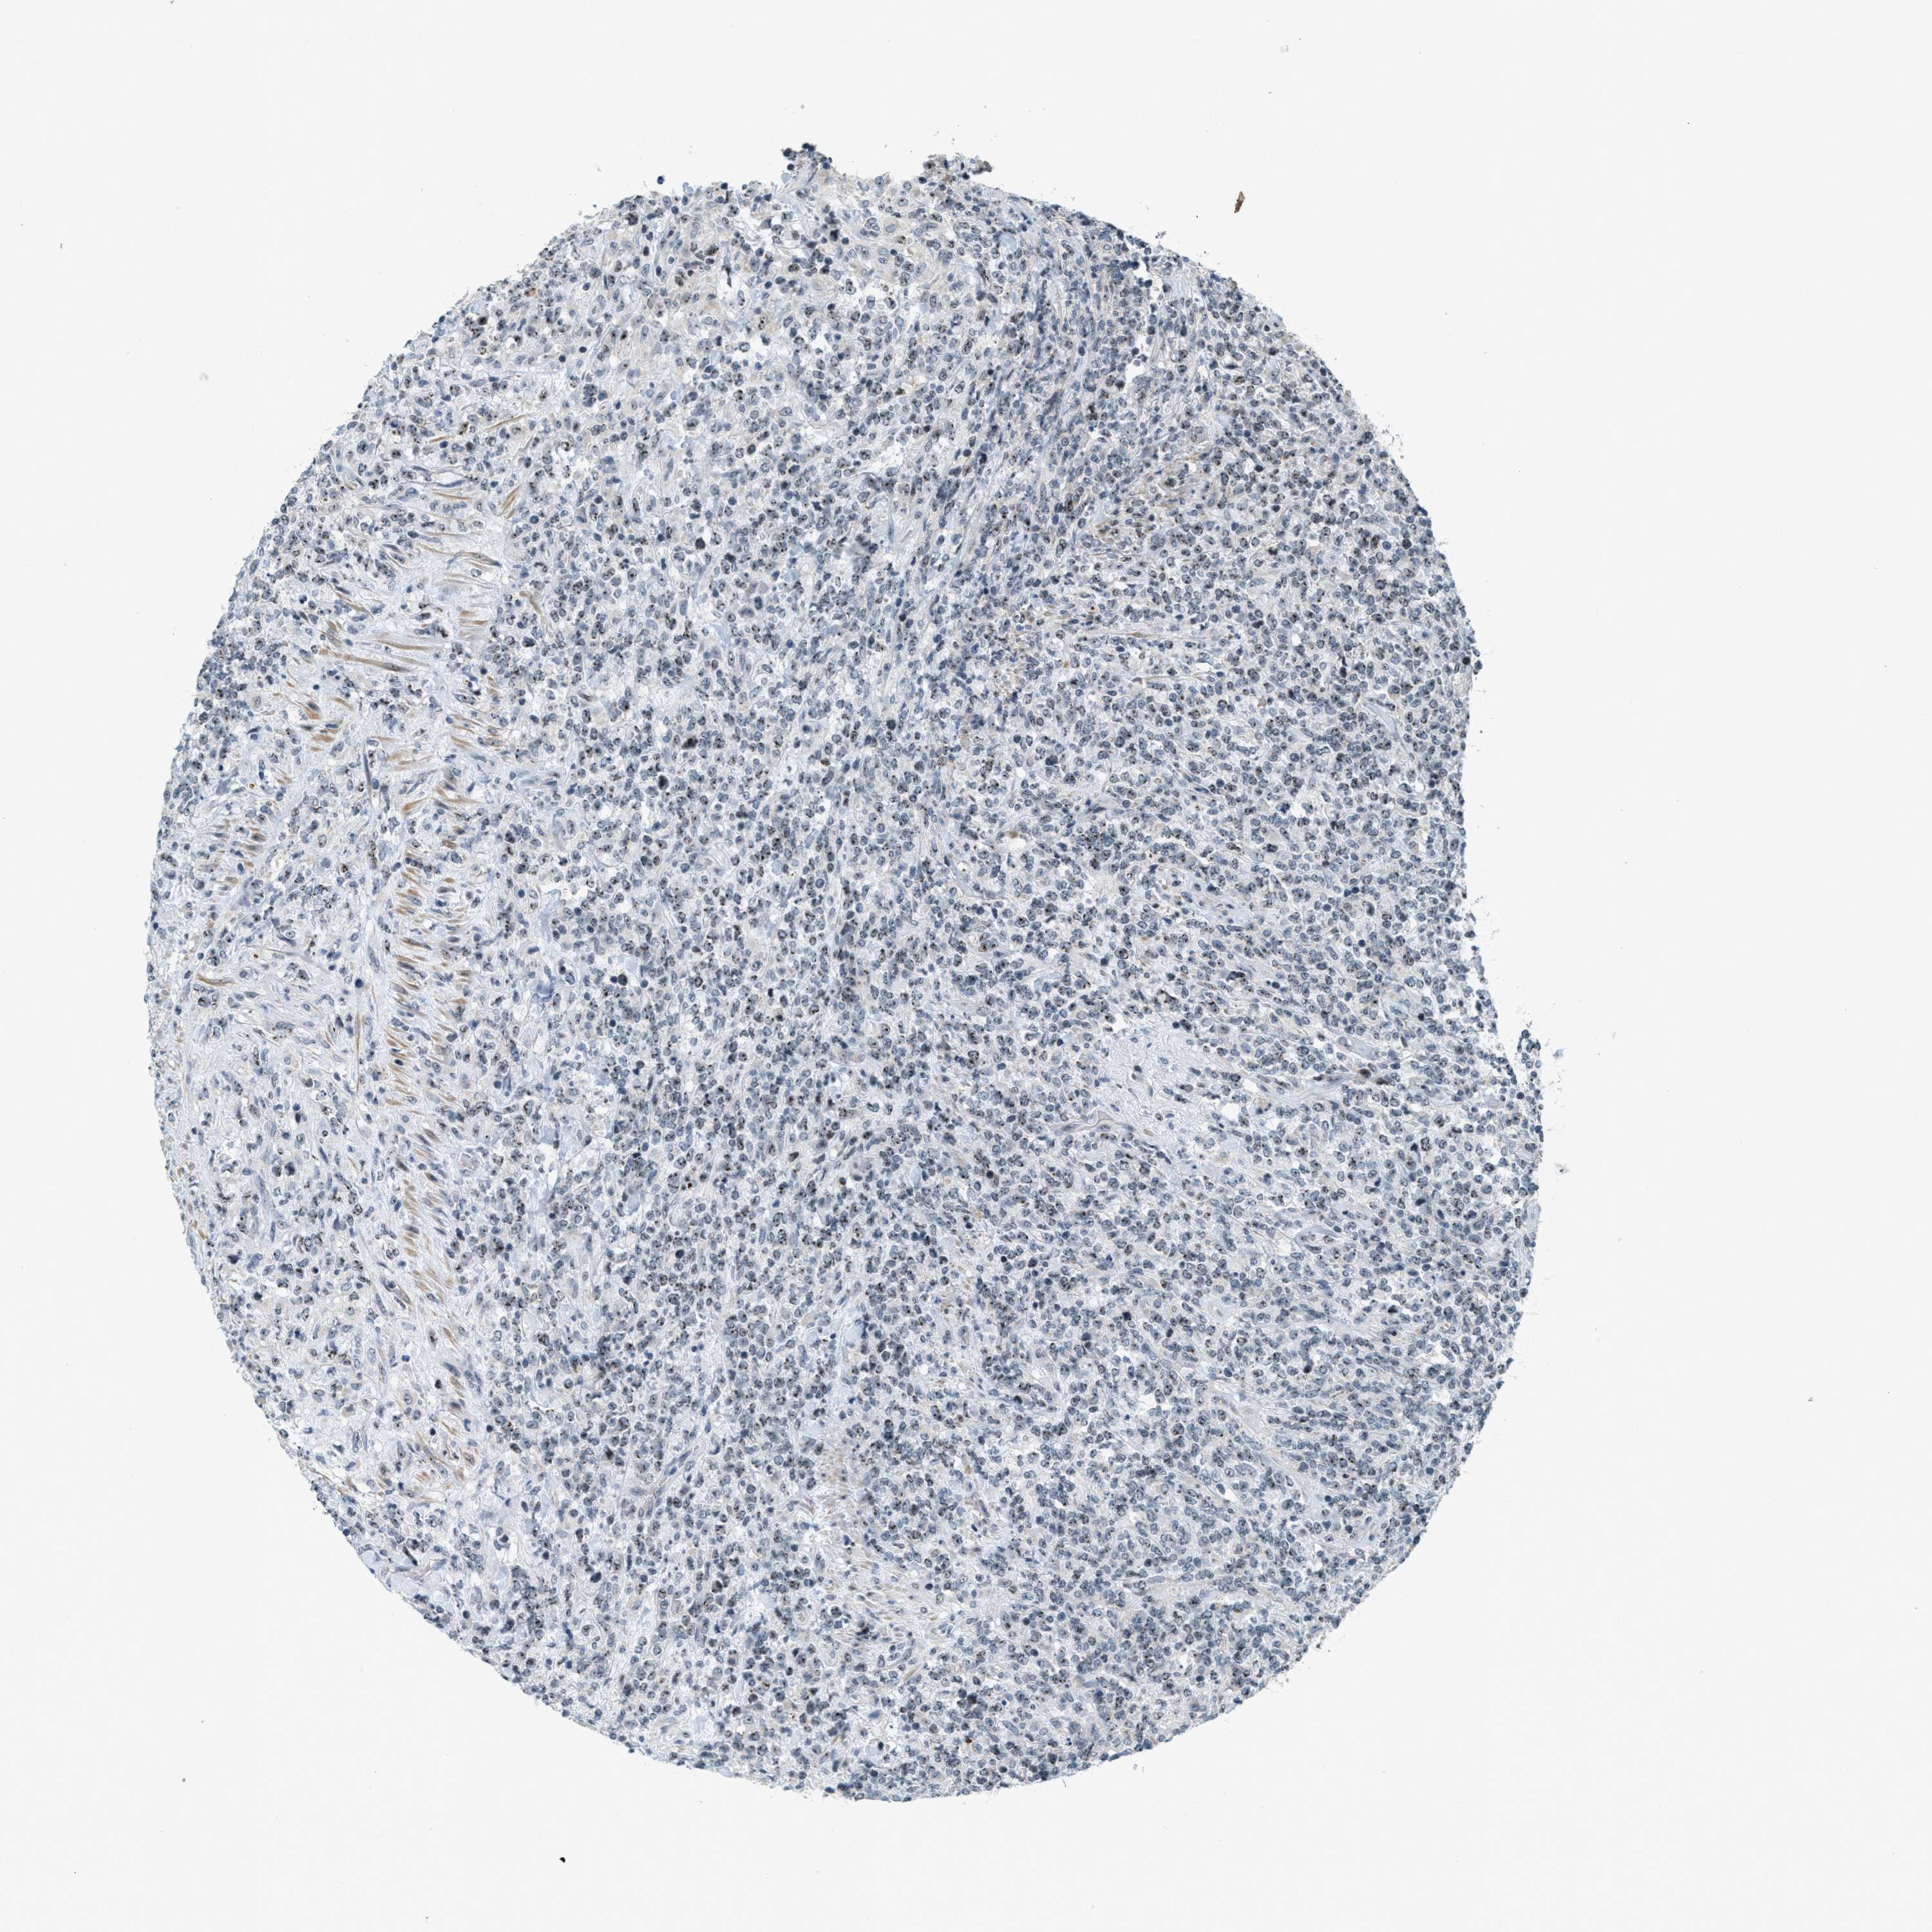

LYMPHOMA - Protein expressioni

A mouse-over function shows sample information and annotation data. Click on an image to view it in a full screen mode. Samples can be filtered based on level of antibody staining by selecting one or several of the following categories: high, medium, low and not detected. The assay and annotation is described here.

Antibody stainingi

Antibody staining in the annotated cell types in the current human tissue is reported as not detected, low, medium, or high, based on conventional immunohistochemistry profiling in selected tissues. This score is based on the combination of the staining intensity and fraction of stained cells.

Each image is clickable and will lead to virtual microscopy that enables deeper exploration of all samples and also displays staining intensity scores, fraction scores and subcellular localization as well as patient and tissue information for each sample.

Antibody HPA014855

Hodgkin's disease, NOS

Malignant lymphoma, non-Hodgkin's type, High grade

Malignant lymphoma, non-Hodgkin's type, Low grade